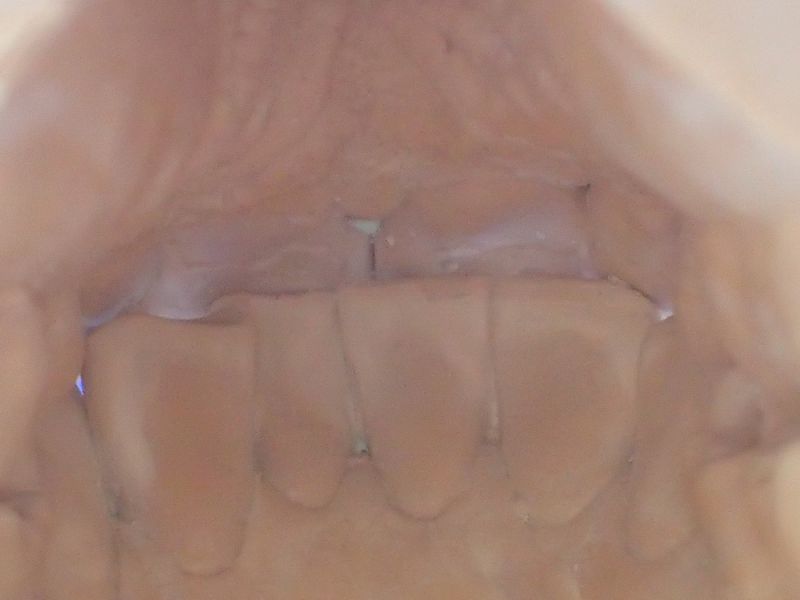

Patientin von der dänischen Grenze erhält einen adjustierten Aufbissbehelf